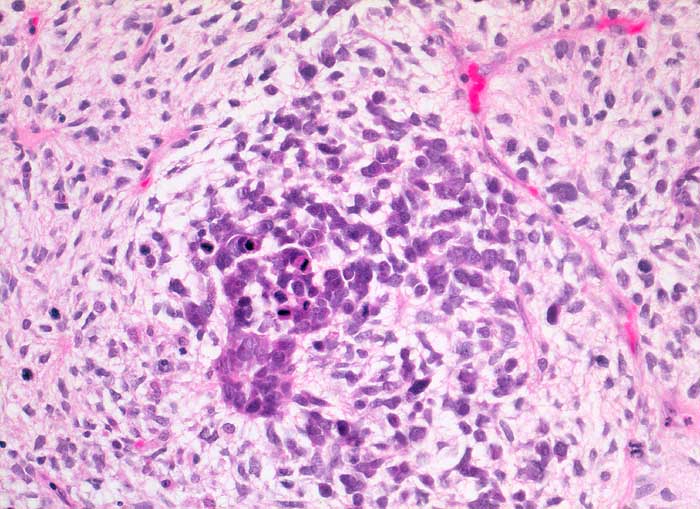

Maligner Müllerscher Mischtumor des Ovars

Müllersche Mischtumoren bestehen aus einer epithelialen und einer mesenchymalen Komponente. Die epitheliale Komponente ist in der Regel ein Adenokarzinom. Die Sarkomkomponente kann homolog (Leiomyosarkom, Stromasarkom, Fibrosarkom) oder heterolog (Rhabdomyosarkom, Chondrosarkom...) sein also nicht aus ortsständigem Mesenchym entstammend. Am häufigsten treten diese Tumoren im Uteruscavum auf. Sie können aber auch in anderen Lokalisationen des Genitaltrakts vorkommen. Die Ausstriche enthalten ein buntes Zellbild mit deutlich atypischen Zellen. Wenn neben Karzinomzellen auch atypische mesenchymale Zellen vorhanden sind, kann zytologisch die Diagnose eines malignen Müllerschen Mischtumors gestellt werden.